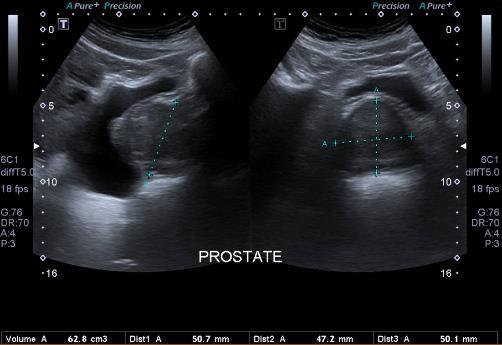

Sonar

Ultrasound imaging, also called sonography, uses sound waves to produce ultrasound images of the inside of the body. An instrument called a transducer emits high-frequency sound, inaudible to human ears, and then records the echoes as the sound waves bounce back to determine the size, shape, and consistency of soft tissues and organs. It is used to help diagnose the causes of pain, swelling and infection in the body's internal organs, joints and tendons. Doppler ultrasound is used to evaluate the arteries and veins to diagnose obstructions or blood clots also vascular malformities. Ultrasound is safe, noninvasive, and does not use ionizing radiation. Ultrasound is useful for guiding biopsy procedures.